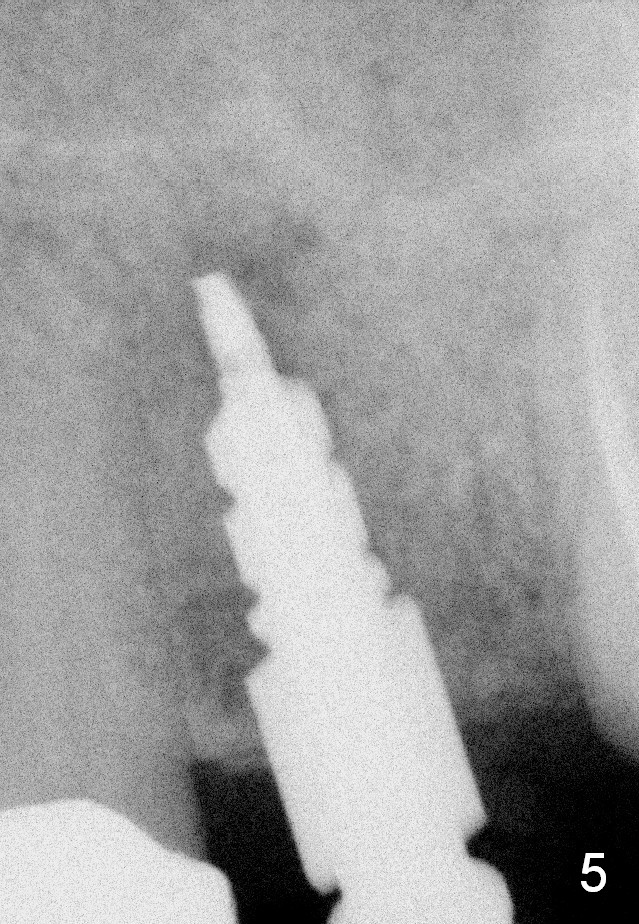

A 45-year-old lady is nervous about dental treatment. The missing tooth #13 was replaced by a 3-unit bridge. The latter is sectioned because the posterior abutment has caries. PA in Fig.1 is taken when root canal therapy and build up are finished. Fig.2 shows the wide edentulous area with a single-unit crown being tried in for #14. Osteotomy is initiated with the crown in place without cementation, since it is easy to determine the mesiodistal position (Fig.3 red lines). Without the crown in place, osteotomy tends to be distal. In this case, the osteotomy is later attempted to be moved distally with Lindamann bur and deepened to 14 mm from the gingival margin (Fig.4). A 2.5 mm reamer is being used at 50 RPM to increase osteotomy with difficulty. Drills have to used at high RPM instead (Fig.5 4x14 mm). A 4.5x14 mm tissue-level implant is placed with insertion torque >60 Ncm (Fig.6 I); a 4x3 mm abutment (A) is placed immediately for an immediate provisional. Fig.7 is taken 7 days postop to show the gingival recipient site formed by the provisional. The patient is so afraid of X-ray that the next one is taken 1.5 years post cementation (Fig.8). It appears that dense bone bundle forms between the crest and the 1st implant thread (adaptation functional change, arrowheads). The bone density continues to increase 2 years 8 months post cementation (Fig.9 *, 10); the bone has grown into the area between the 1st 2 threads (arrow).